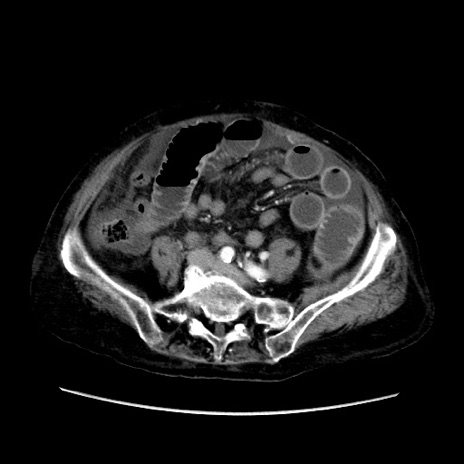

症例31(横断像)

【症例】80歳代 女性

【主訴】腹部膨満感

【現病歴】他院にて肝硬変にてフォロー中。1週間前から便秘、腹部膨満感、臍部腫瘤あり受診となる。

【既往歴】肝硬変

【身体所見】腹部膨隆あり、皮膚変化なし、疼痛なし。

【データ】WBC 4600、CRP 0.25